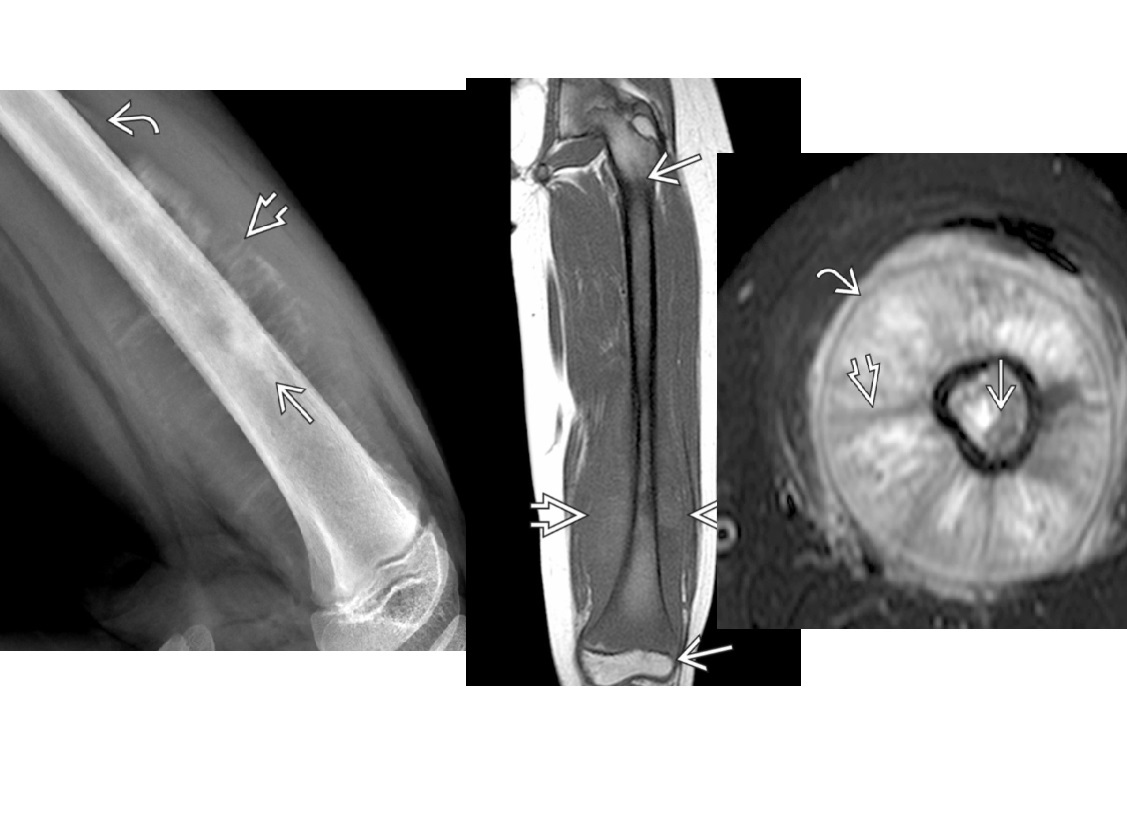

Osteoid osteoma

Cortically based

peripheral sclerosis and central with nidus

**nidus > 2cm = osteoblastoma **

= Posterior elements

Nb** Osteoblastoma can have have soft tissue expansion/involvement**

Double density bone scan

DDx

-stress fracture

- intracortical abscess